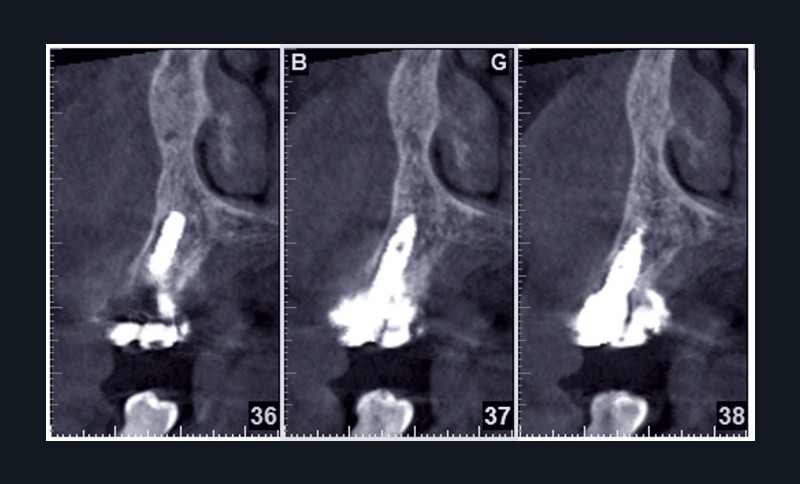

Cette ostéointégration est confirmée par le Cone Beam(fig. 4a et b).